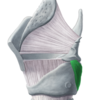

Which muscle is this?

A

Inferior constrictor